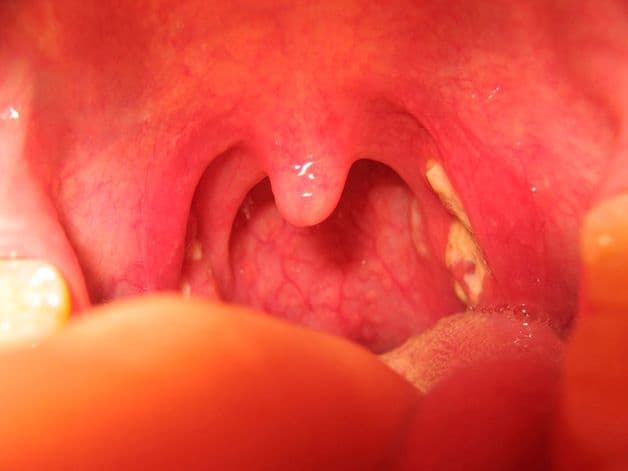

Bệnh viêm amidan hốc mủ thường không khó có thể nhận biết. Để nhận diện bệnh, ta hãy thông qua những triệu chứng đặc hiệu. Điển hình như:

– Những triệu chứng nhận biết đầu tiên: cảm giác đau họng và nuốt vướng, tăng tiết dịch nước bọt, xuất hiện hạch cứng, đau tại vùng cổ hoặc xương hàm, những triệu chứng đau lan từ vùng họng lên tai, …

– Triệu chứng bị viêm amidan có hốc mủ cấp tính: Sốt cao từ 38.5 độ C, cảm giác đau ngực, khó thở, mất tiếng, giọng nói bị thay đổi, bệnh nhân ho nhiều, có đờm, lưỡi trắng, phần amidan sưng to gây cản trở đường thở, …

Viêm amidan có hốc mủ thường có những triệu chứng khá dễ nhận biết. Do vậy nên mọi người có thể tham khảo các thông tin trên giúp nhận biết và điều trị bệnh sớm để khắc phục căn bệnh này.